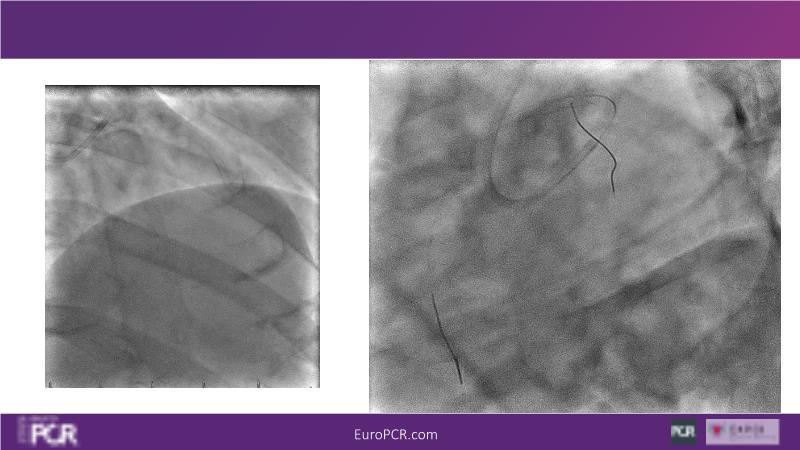

Join this session to delve into the unmet needs concerning drug-eluting stents (DES), including poor long-term clinical outcomes, with up to a 50% MACE rate at 10 years, and a non-plateauing 2-3% annual event rate. Explore how DynamX Bioadaptor technology addresses these challenges by maintaining the established flow lumen and restoring hemodynamic modulation of the artery. Discover the sustained clinical benefits demonstrated in a 2-year RCT, potentially establishing a new treatment standard for CAD patients. Gain insights into patient types benefiting most in clinical practice, such as those at higher risk of restenosis (e.g., LAD disease, long lesions, small vessels, co-morbidities), and younger patients with longer lifespans.